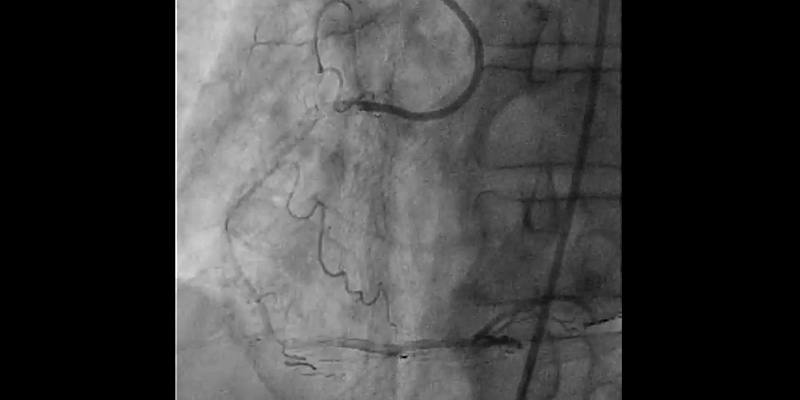

• Right coronary artery showed significant stenosis in the proximal segment (70%), severe calcification of the proximal and mid segments, and critical stenosis in the distal segment (95%)

• LAD with stent in the proximal segment without restenosis. Mid LAD showed severe calcification with a significant stenosis - 85% (Medina 1-0-1) involving the diagonal ostium

• Circumflex artery: first obtuse marginal, 70% stenosis. Second obtuse marginal with implanted stent, without restenosis

Syntax score I: 20, Syntax score II PCI: 28.2, CABG 30.5.